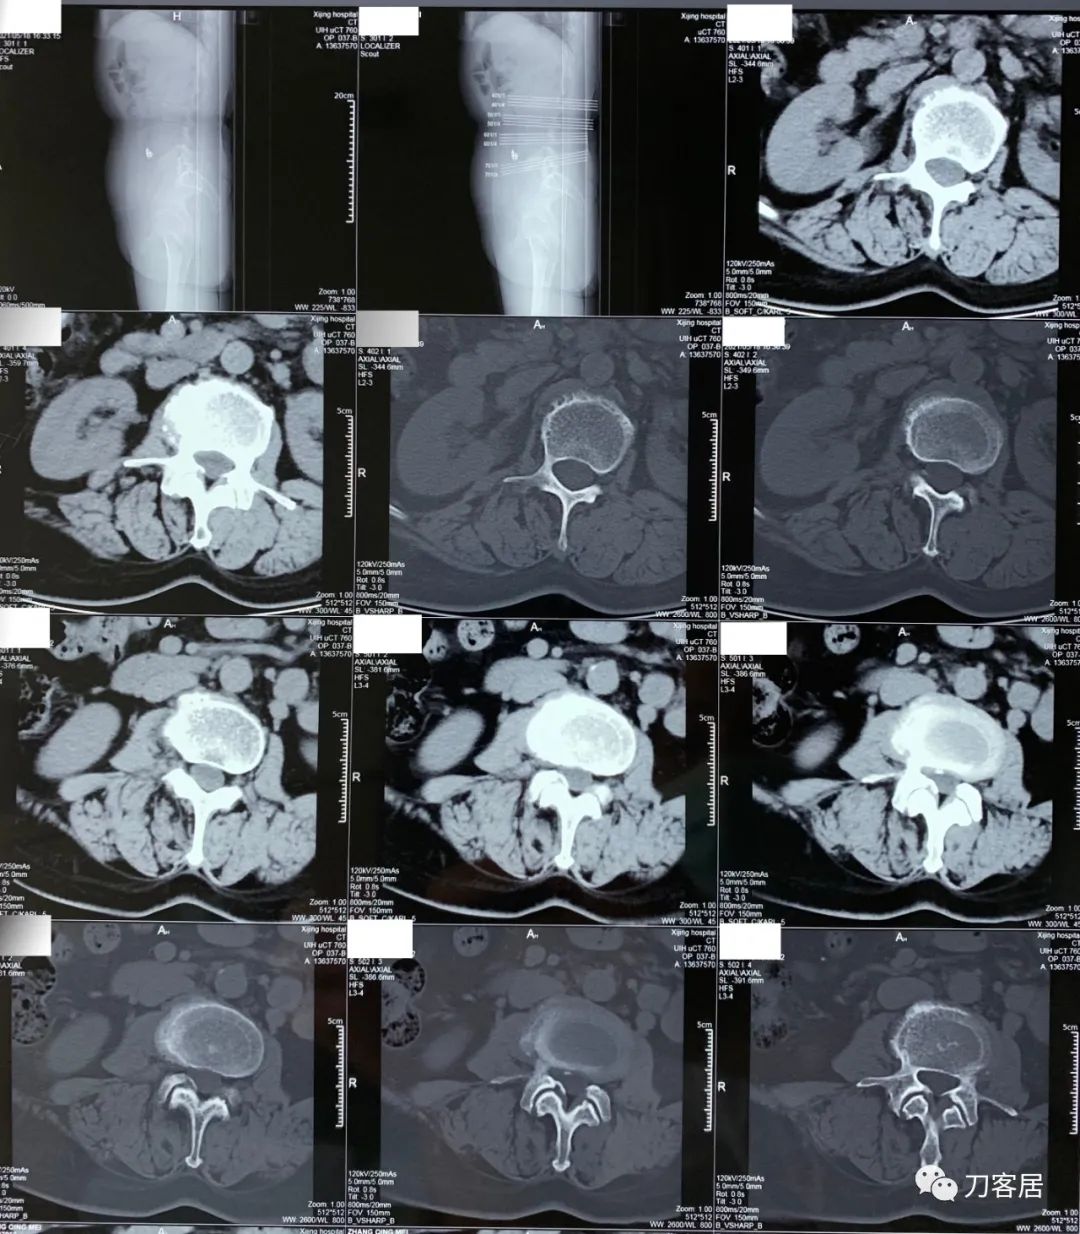

2021年5月17日,西京医院骨科门诊找我就诊,自带影像学检查资料提示腰椎侧弯,腰3-4,腰4-5椎间盘突出,黄韧带肥厚,椎管狭窄。

建议其查双光子骨密度,骨盆正位片以及腰椎间盘平扫。腰椎正侧位X线片以及动力位片,站立位脊柱全长正侧位X线片,以了解其是否有骨质疏松,并了解脊柱侧弯情况,腰椎局部X线表现情况和腰椎间盘突出和椎管狭窄情况。

从这个患者的影像资料分析,颈椎间盘突出问题不大,没有明确的上位神经元损伤表现,所以,不考虑颈椎和胸椎问题。腰椎侧弯畸形,但不严重。因为存在腰椎侧弯,使得腰椎MRI在扫描切面的时候,显示的椎间盘突出或椎管狭窄会有一定的误差,所以,又加做了经椎间盘的CT平扫,影像表现并不严重,综上,腰椎间盘突出,腰椎管狭窄,腰椎侧弯,不考虑手术治疗。同时,患者的主要痛苦是心理疾病,而不是器质性疾病,所以,以心身疾病治疗为主。虽然患者骨密度检查结果提示正常,但X线片显示骨质疏松,且其症状也与骨质疏松的症状有符合之处,比如静息痛,不能入睡,动作及姿势变换时痛加重等,所以,给予实验性抗骨质疏松治疗,以观疗效。